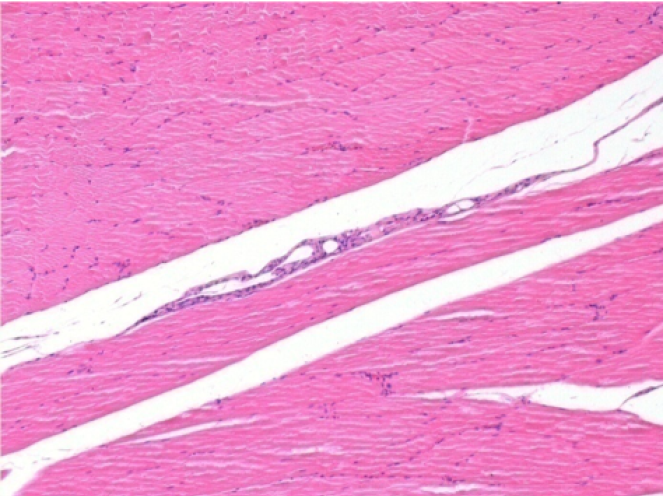

10 días después de la inyección de Endopeel

10 días después de la inyección de Endopeel 0,1 ml en el músculo pretibial derecho.

Aquí puede ver la formación de las vacuolas que están rodeadas de linfocitos. Las vacuolas son diferentes a la necrosis tisular. La presencia de linfocitos está relacionada con la permeabilidad de las membranas celulares.

L : Control-100xD10

R:100xD10

R :200xD10

R :400xD10